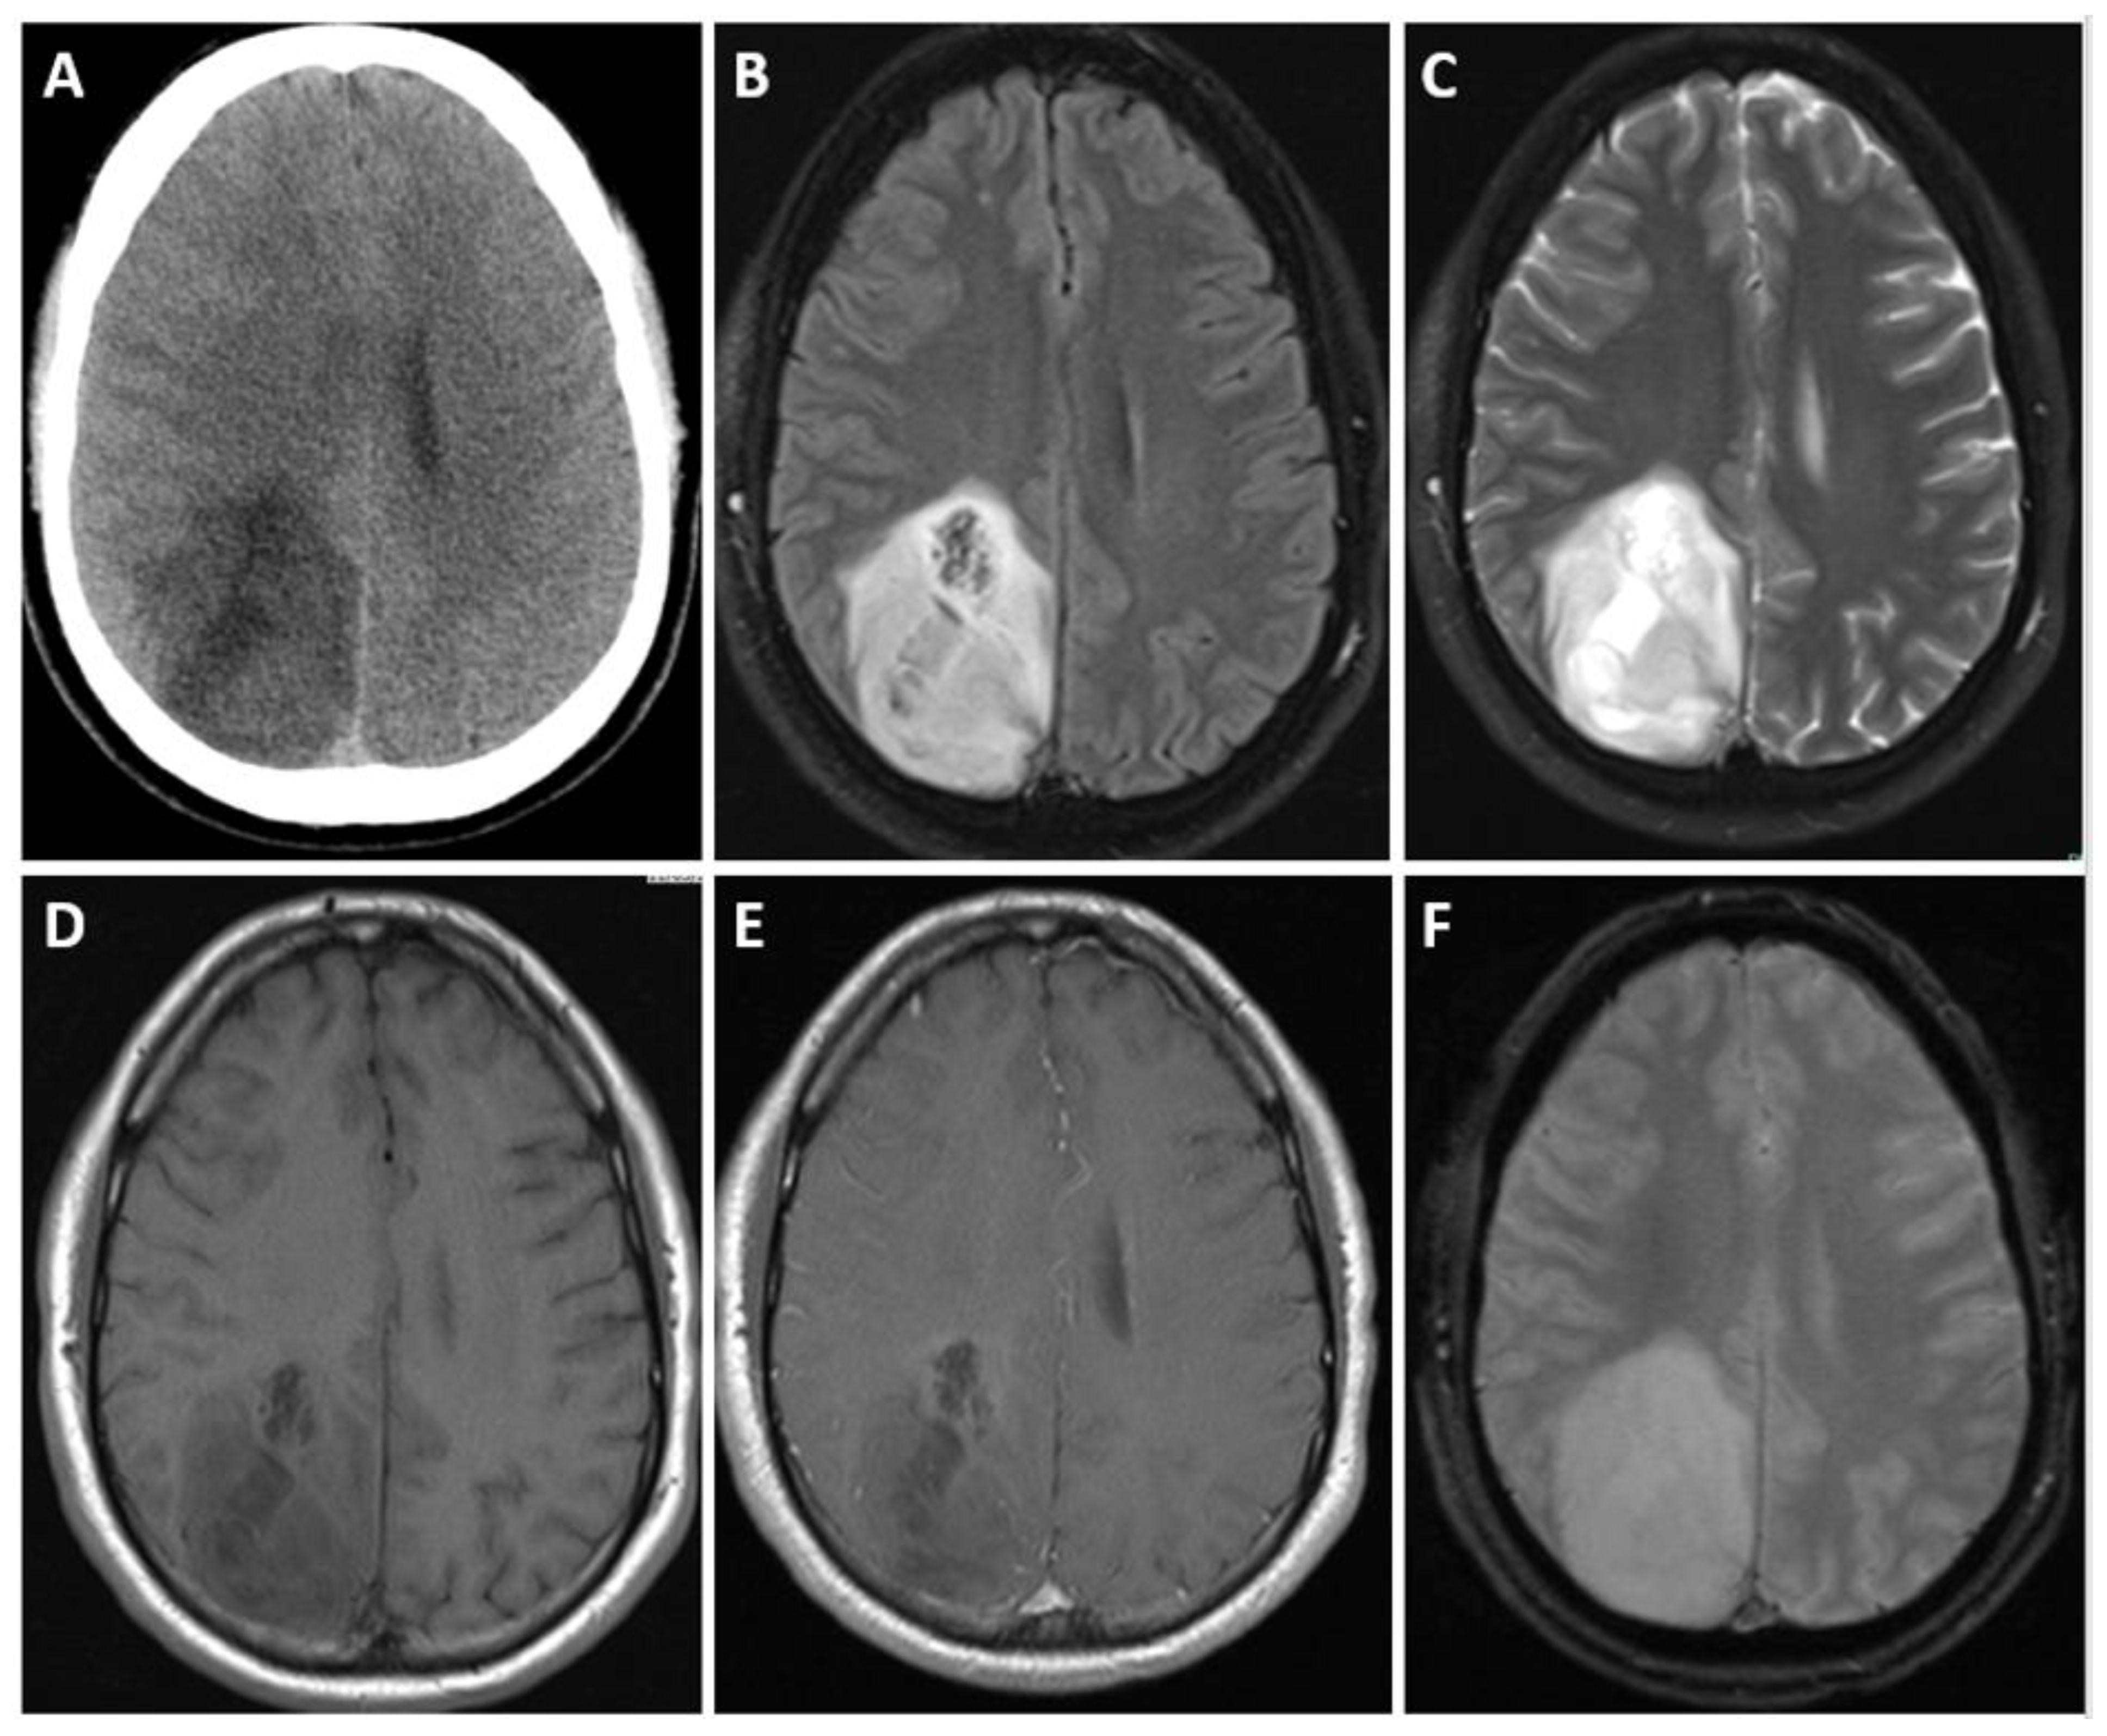

- Carrillo, J.; Lai, A.; Nghiemphu, P.L.; Kim, H.J.; Phillips, H.S.; Kharbanda, S.; Moftakhar, P.; Lalaezari, S.; Yong, W.; Ellingson, B.M.; et al. Relationship between Tumor En-hancement, Edema, IDH1 Mutational Status, MGMT Promoter Methylation, and Survival in Glioblastoma. Am. J. Neuroradiol. 2012, 33, 1349–1355. [Google Scholar] [CrossRef]

- Fan, H.; Yu, Y.; Du, J.; Liu, L.; Luo, Y.; Yu, H.; Liao, X. Computed Tomography, Magnetic Resonance Imaging, and Pathological Features of Gliosarcoma. Neuropsychiatr. Dis. Treat. 2022, 18, 2577–2589. [Google Scholar] [CrossRef] [PubMed]

- Drumm, M.R.; Dixit, K.S.; Grimm, S.; Kumthekar, P.; Lukas, R.V.; Raizer, J.J.; Stupp, R.; Chheda, M.G.; Kam, K.-L.; McCord, M.; et al. Extensive brainstem infiltration, not mass effect, is a common feature of end-stage cerebral glioblastomas. Neuro-Oncology 2020, 22, 470–479. [Google Scholar] [CrossRef] [PubMed]

- Niyazi, M.; Brada, M.; Chalmers, A.J.; Combs, S.E.; Erridge, S.C.; Fiorentino, A.; Grosu, A.L.; Lagerwaard, F.J.; Minniti, G.; Mirimanoff, R.O.; et al. ESTRO-ACROP guideline “target de-lineation of glioblastomas”. Radiother. Oncol. 2016, 118, 35–42. [Google Scholar] [CrossRef] [PubMed]

- Thomas, R.P.; Xu, L.W.; Lober, R.M.; Li, G.; Nagpal, S. The incidence and significance of multiple lesions in glioblastoma. J. Neuro-Oncol. 2013, 112, 91–97. [Google Scholar] [CrossRef]

- Farhat, M.; Fuller, G.N.; Wintermark, M.; Chung, C.; Kumar, V.A.; Chen, M. Multifocal and multicentric glioblastoma: Imaging signature, molecular characterization, patterns of spread, and treatment. Neuroradiol. J. 2023. [Google Scholar] [CrossRef]

| Glioblastoma, IDH-wildtype | IDH-wildtype, TERT promotor, +7/−10 chromosome copy number changes, EGFR | Only IDH-wildtype no IDH-mutant, | Inherent heterogeneity, heterogeneously enhancing, sometimes ring- enhancing around central necrosis, surrounding T2/FLAIR signal, edema and mass effect, increased rCBV, surrounding infiltration. |